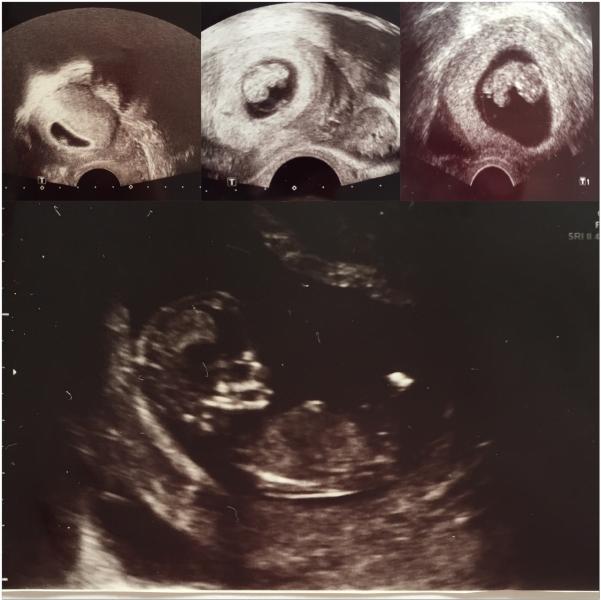

Наш первый скрининг прошёл нормально. Встреча в госпитале была назначена на 10.15 попали мы к ней в 11.20. Ребенок дремал😹 на спинке и явно был не доволен тем, что мы потревожили его/её сон и не хотел переворачиваться, "узистка" стучала слегка по животу и нажимала что бы он/она подвигался😆 малыш ни в какую не хотел показывать свою воротниковую зону. В итоге получилось измерить только 2 раза, хотя по стандарту нужно 3, зато мы наслаждались встречей с малышом достаточно долго. Услышали заветные слова "все в порядке" сдали кровь и отправились домой. Единственное что меня удивило😳 и немного напрягло- это размер нашего/ нашей крохи 13см! А вы помните как прошёл первый скрининг? Какого размера был ваш малыш? 💕🍼🇨🇭